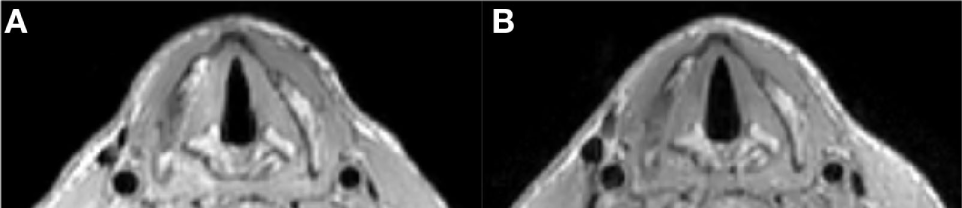

A comparison between the setups shown in Figure 1A (two commercial loops) and Figure 2A (dedicated coil) is shown in Figure 3. The scan with the loops placed on a cooperative volunteer was acquired with an acceleration factor of two (the maximum achievable factor for a two-element coil), while the scan with the dedicated coil was performed with an acceleration factor of three. The image quality between the two setups is very similar (when the two commercial loops are perfectly positioned), but the scan with the dedicated coil could be performed with a 33% reduction in scan time. The images show that the dedicated coil outperforms the commercially available setup even under ideal scanning conditions.

Figure 3

Respiratory triggered T1 TSE sequence (1 mm isotropic voxel size) with parameters as in Table 1. (A) Shows an image at the level of the vocal cords made with the two loops setup (as in Figure 1A) and at the maximum acceleration factor of 2.0: total scan time 234 s. (B) Shows an image at the same level made with the dedicated coil and an acceleration factor of 3.0: total scan time 189 s.

Figure 4 shows a comparison of images acquired with and without respiratory triggering. Respiratory triggering obviously increases the total imaging time, but the acceleration factor of three using the dedicated coil array reduces the scan time to 3 min and results in images without breathing and swallowing motion artifacts while at the same time also improving general image quality.

Figure 4

T1 TSE multi-slice sequence (transversal) at 1.0 mm isotropic resolution with SPIR fat suppression (scan parameters in Table 1) (A) without respiratory trigger, duration 57 s, (B) with respiratory trigger, duration 216 s. Triggering mitigates breathing and swallowing motion artifacts and increases image quality.